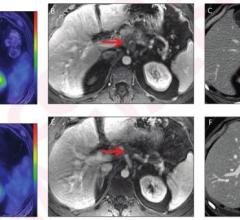

Feb. 4, 2026 — A new review published in the American Journal of Roentgenology (AJR) finds that advances in CT ...